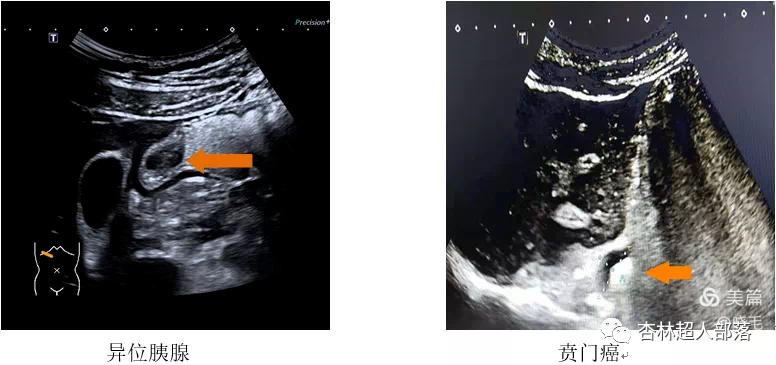

下面我们看看胃肠超声扫描出来的

这些典型病例图像吧。